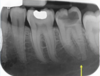

88

is the following periapical pathology or not?

no

89

yes - lamina dura tracking off

90

no PDL widened probs cus of brace

91

yes